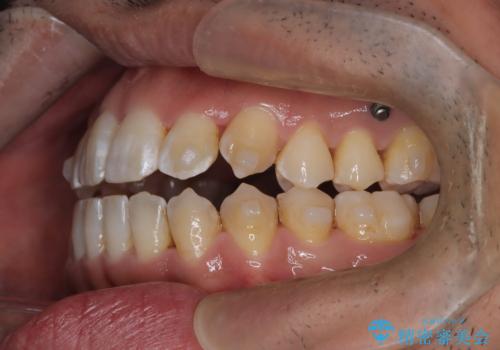

- 左上の八重歯を気にされて来院されました。精密な検査の結果、歯列全体を広げながら八重歯を奥へ移動させることで、美しい歯並びと機能的な咬み合わせが得られると診断。患者様のご希望に合わせ、透明で目立ちにくい**インビザライン(マウスピース矯正)**による治療計画を立案しました。抜歯を避け、歯を少しずつ遠心(奥)へ移動させることで、歯が並ぶスペースを確保し、叢生(歯のデコボコ)を改善します。

今回の矯正治療では、透明なマウスピース型の装置インビザラインを使用しました。この装置は目立ちにくく、取り外しが可能なため、食事や歯磨きも普段通りに行えます。遠心移動という方法で奥歯を後方に動かし、前歯を並べるためのスペースを確保。これにより、抜歯することなく、左上の八重歯を含む叢生を効果的に改善し、整った美しい歯並びと良好な咬み合わせを獲得していただけました。